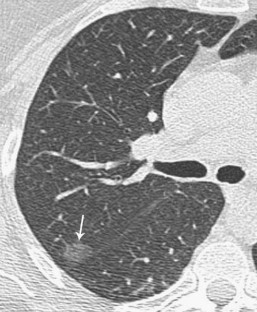

Fig. 3